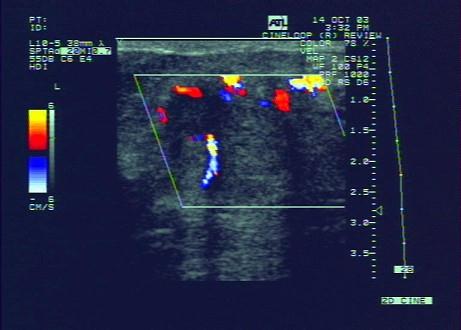

问题 乳腺癌CDFI特点是?(?)

选项 A.无血流信号 B.彩色血流不丰富,血管数目少 C.彩色血流丰富,呈高速低阻血流 D.彩色血流丰富,呈高速高阻血流 E.彩色血流不丰富,呈高速低阻血流

答案 D